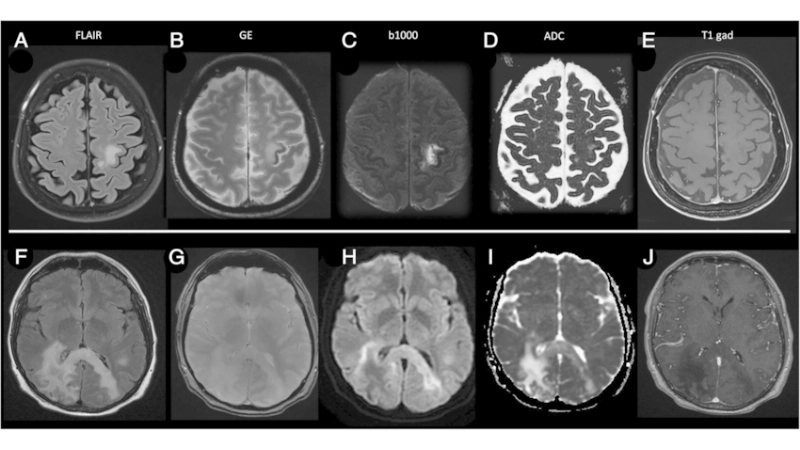

PML diagnosis relies on MRI and JC virus detection